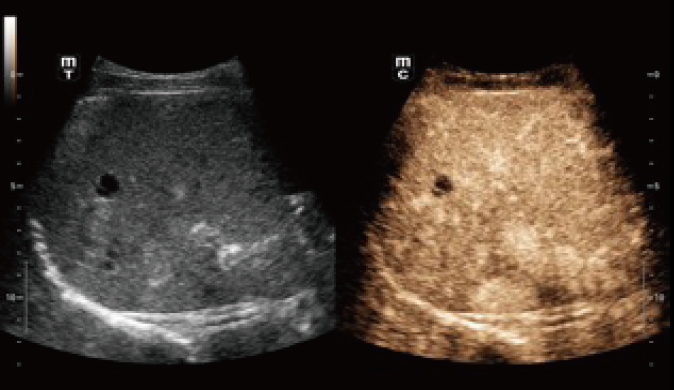

Das Resona I8 weist vielfältige klinische Lösungen auf, die speziell für den jeweiligen Anwendungsbereich entwickelt wurden. Die Technologie baut auf einem tiefgreifenden Verständnis verschiedener klinischer Szenarien auf und bietet eine umfassende Serie fortschrittlicher Diagnoseinstrumente, beispiellose Intelligenz und präzise Analysen zur Verbesserung von Diagnosesicherheit, Qualitätskontrolle und Scaneffizienz.